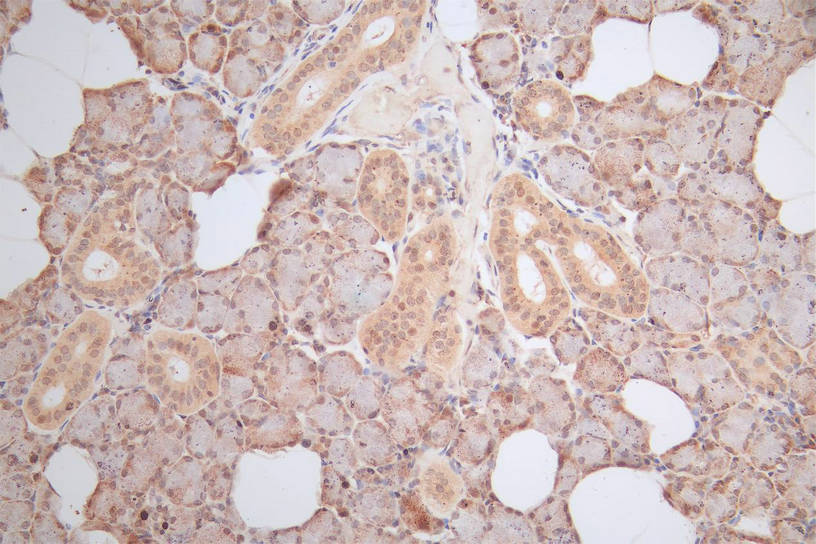

IHC image of CSB-RA010553MA1HU diluted at 1:100 and staining in paraffin-embedded human salivary gland tissue performed on a Leica BondTM system. After dewaxing and hydration, antigen retrieval was mediated by high pressure in a citrate buffer (pH 6.0). Section was blocked with 10% normal goat serum 30min at RT. Then primary antibody (1% BSA) was incubated at 4°C overnight. The primary is detected by a Goat anti-Mouse IgG labeled by HRP and visualized using 0.05% DAB.